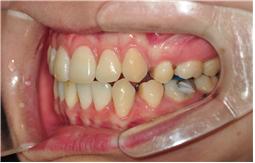

이번 교정치료는 와이어교체입니다~

먼저 사진촬영부터 시작~

엑스레이 앞면 옆면 사선 찍공

일반사진 찰칵찍고~ 아직도 거의 쌩얼인지라

그래도 발치공간은 조금씩 닫히고 있는 거 같습니다~